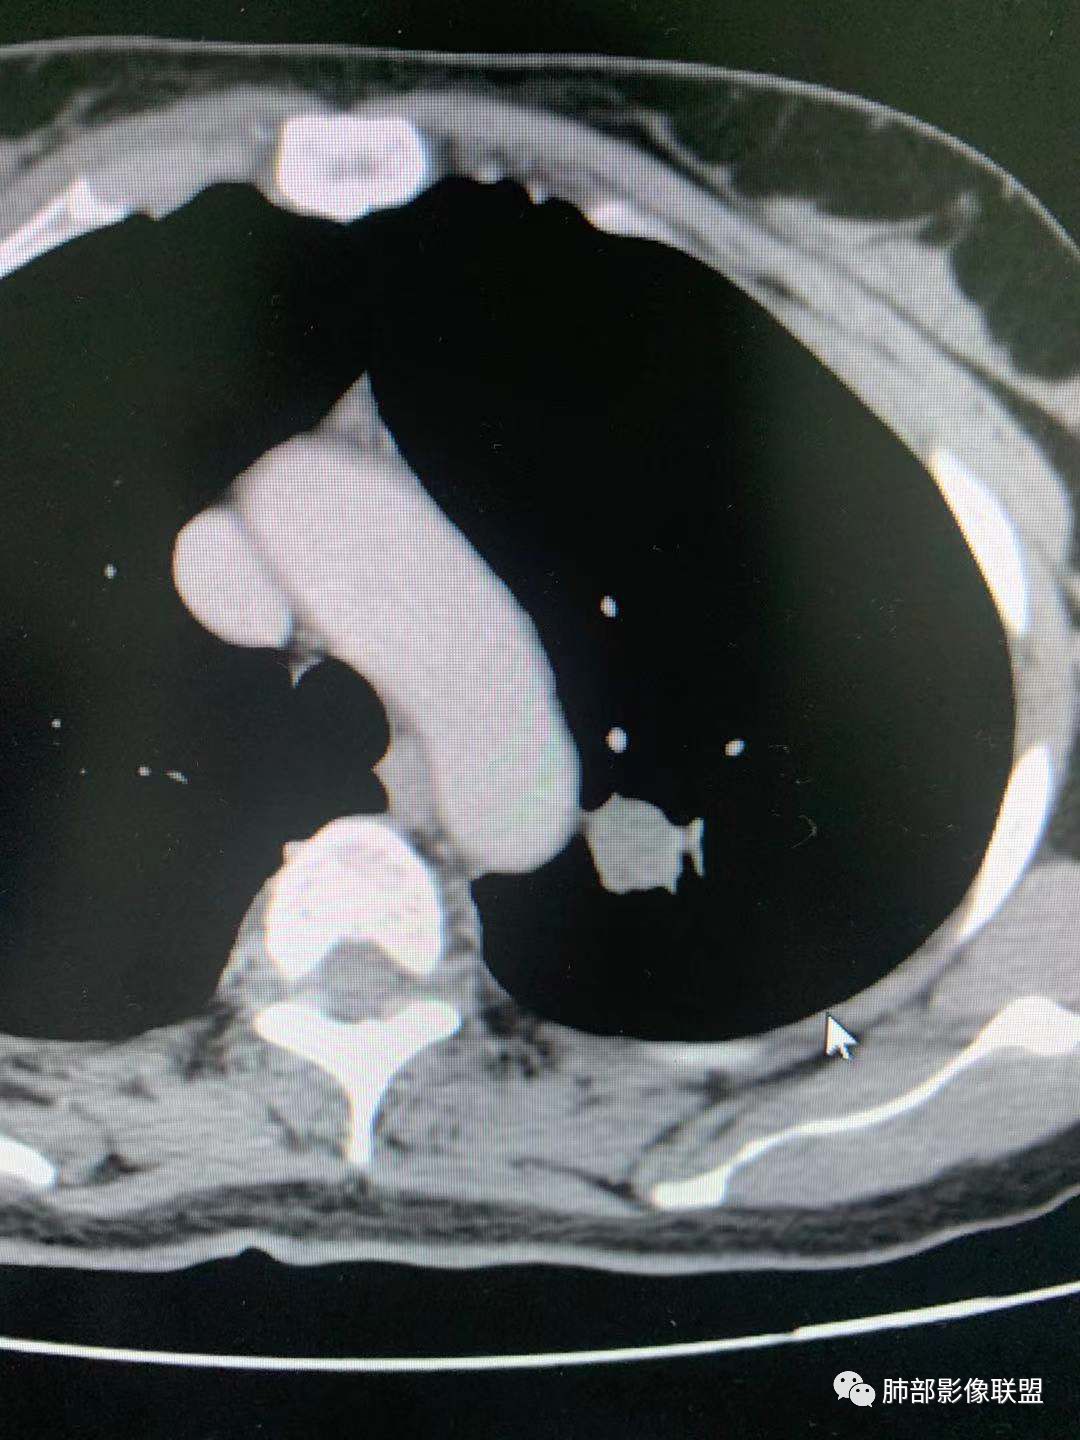

四、

这个怎么分析?

大家都考虑PSP?理由?

腺癌吧

有棘状突起,强化渐进性,强化了四十左右

凝睦

周围有边界清楚磨玻璃密度,腺癌

CT值30HU;增强后:41/76HU

强化幅度:46HU

蓝天白云

周围有边界清楚磨玻璃晕

无胸膜牵拉

收缩力弱

1、边界清不清?

我觉得不清楚

有血管进入,清

边缘平直,延迟强化,血管贴边,支气管推移,毛刺较软,收缩力较弱。

血管贴边

大部分清,有小部分模糊

最上部层面,血管杂乱无章

增粗扭曲

2、形态规则吗?

边缘粗毛刺

类圆形

规则

如果这样,大家下一步应该观察啥?

旁边支气管倒是好像没有明显变窄。倾向于惰性腺癌,需要与psp鉴别

与支气管关系

长毛刺

啥关系啊?

从边绕过

支气管靠外侧,无明显变窄

好像是挤压,最好做重建

图不足啊,需要补充

这两条交代清楚了

这一条?

欣

走形自然,无变窄,无明显侵犯

堵了?还是边上走了?

没堵

堵了是如何堵的?

如果支气管堵了,考虑PSP几率就很小

所以我需要补充这个的重建

看清楚这条支气管

还是有收缩力

周围GGO不均匀,边界偏清

是的,有胸膜凹陷

我认为有粗大短毛刺,我之前说成了棘状突了

大结节的支气管应该堵了

远端没看到走出来

潘老师分析细致入微👍,各位老师也很厉害,提供这个病例的初衷主要是这个大的结节,结节周围边界清楚的GGO,部分边缘毛糙,和支气管关系不大,但还是有不踏实的地方,不要轻易诊断良性。另外肺内多发磨玻璃结节,有的胸膜牵拉,当时是建议随访观察,没想到群里老师都是火眼金睛